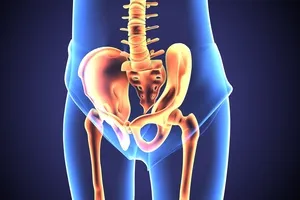

좌골신경통은 좌골신경이 압박되거나 자극받아 발생하는 통증을 말합니다. 좌골신경은 인체에서 가장 길고 큰 신경으로, 허리 아래쪽에서 엉덩이를 지나 다리 뒤쪽까지 이어집니다.

고관절은 우리 몸에서 가장 크고 중요한 관절 중 하나로, 상체와 하체를 연결하며 걷기, 앉기, 서기와 같은 일상적인 움직임을 가능하게 합니다. 하지만 다양한 요인으로 인해 고관절 통증이 발